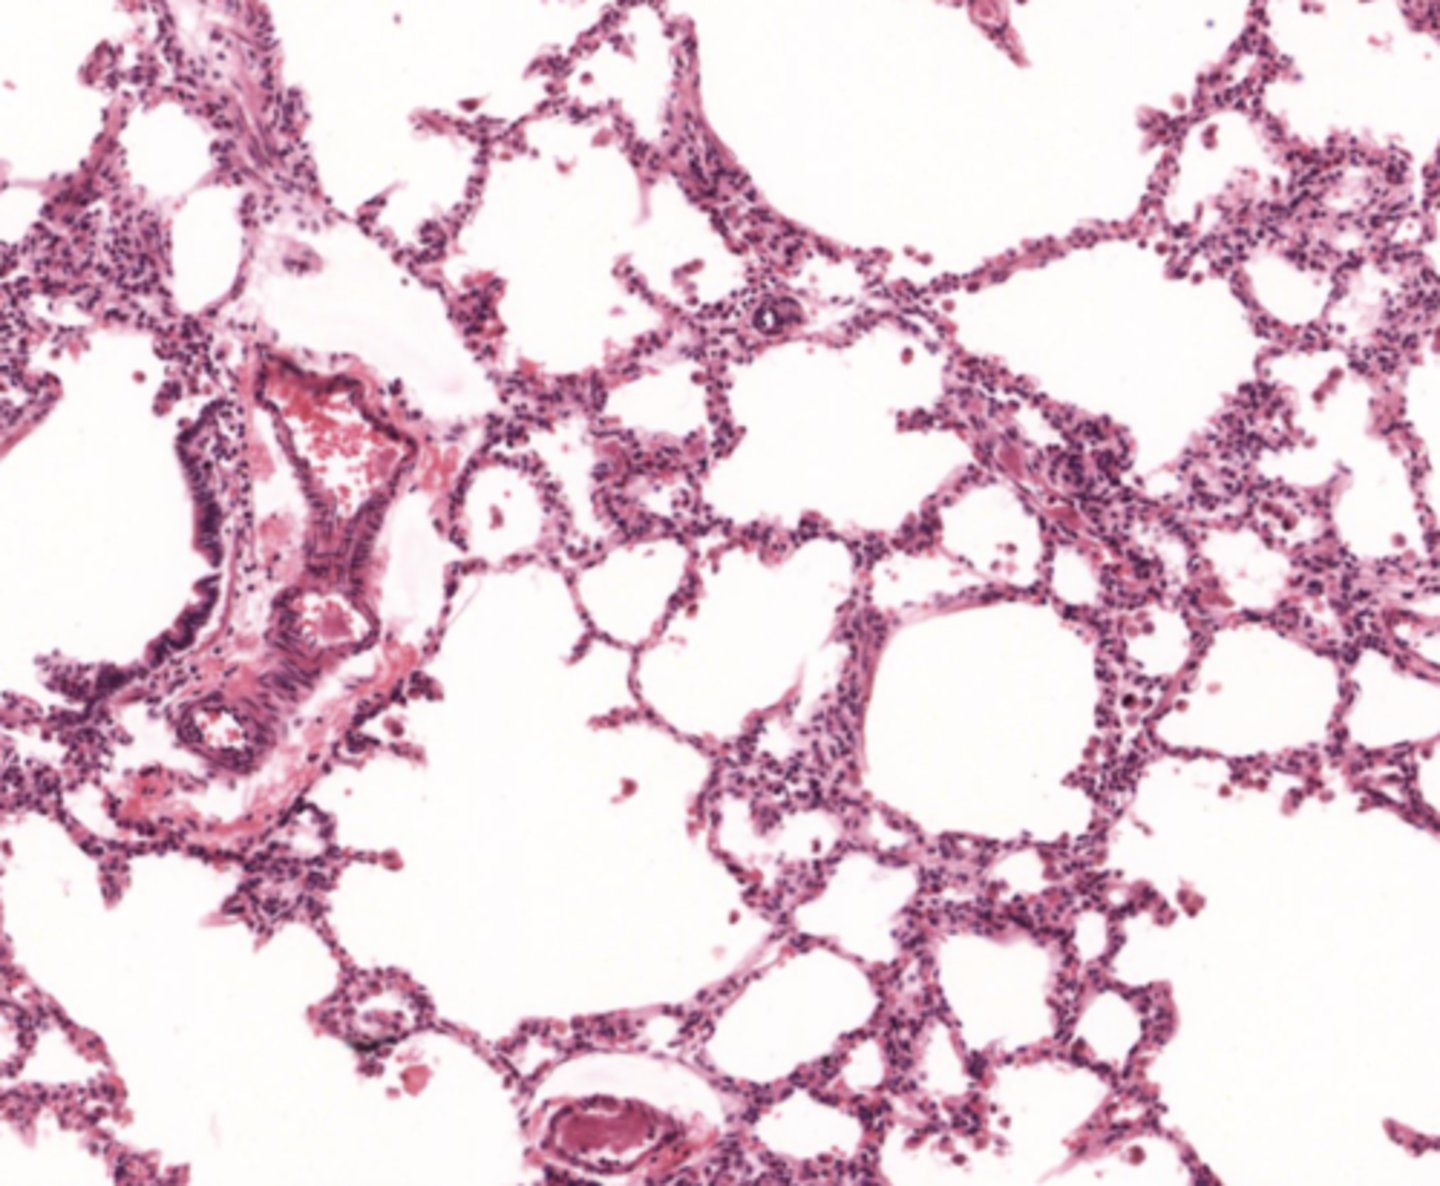

lung (normal)

alveolus (normal)